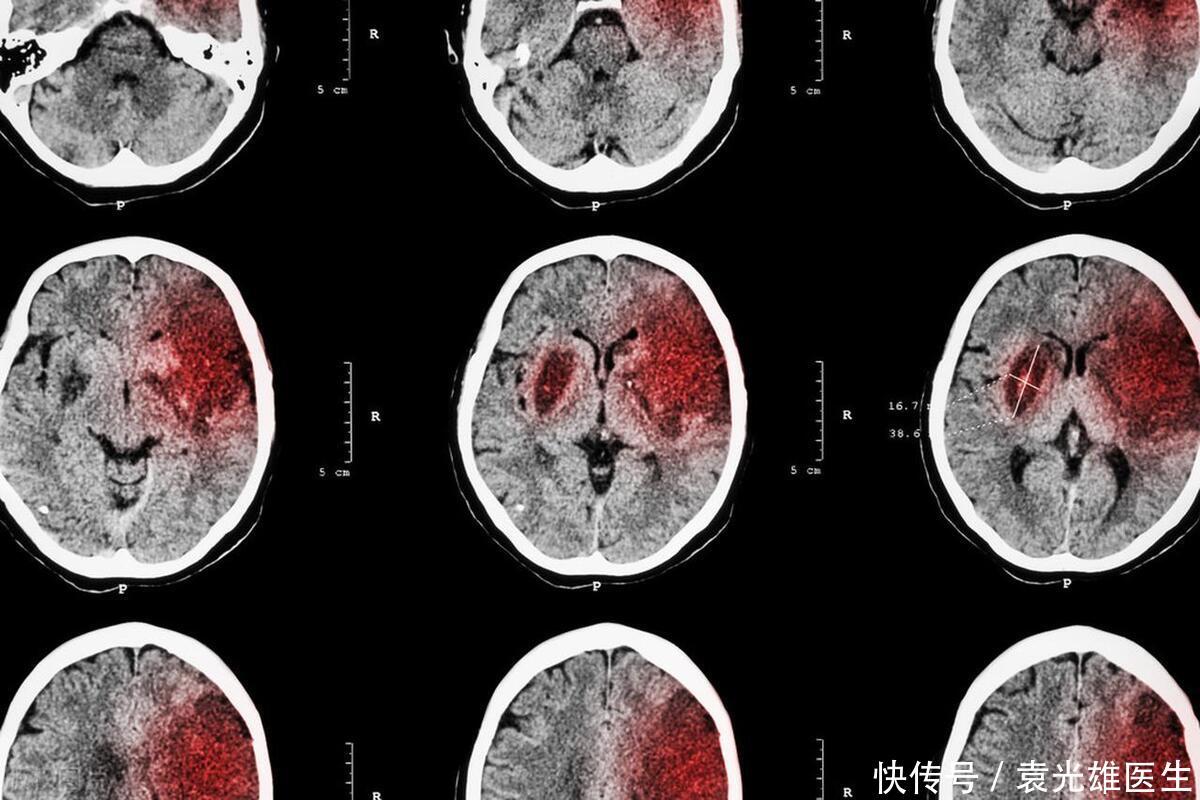

?在现代社会中,脑梗塞已成为威胁人类健康的重大疾病之一。脑梗塞,通常称为“中风”,是由于脑部血管阻塞或破裂导致脑组织损伤,进而影响身体功能。虽然脑梗塞的成因复杂,涉及遗传、环境、生活方式等多个因素,但越来越多的证据表明,不健康的饮食习惯是导致脑梗塞的主要可控因素之一。特别是,某些类型的早餐,因其高盐、高脂、高糖和高热量的特性,被认为是血管堵塞的“帮凶”。本文将探讨四种可能增加脑梗塞风险的早餐食物,并提供健康的饮食建议。